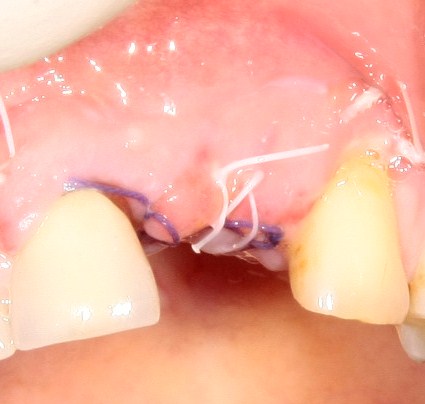

Трансплантация десны, аугментация лунки

Для определения размеров будущего мягкотканного аутотрансплантата мы использовали пародонтологический зонд. С помощью него мы выбрали донорскую зону (бугор верхней челюсти или небная сторона альвеолярного отростка верхней челюсти в области моляров), с помощью скальпеля получили необходимый по размеру аутотрансплантат (мягкотканный лоскут для пересадки).

Затем, мы подготовили ксенографт Bio-Oss Collagen. Обычно на 2 зуба (центральных резца) с избытком хватает 100-миллиграмовой упаковки. Имеющийся в ней параллелепипед мы поделили на 2 усеченные пирамиды с основанием в 2/3 ширины изначального блока.

Если вы когда-нибудь видели подобные операции, то наверняка обращали внимание на порядок действий — сначала устанавливаются имплантаты, затем укладывается графт и только потом фиксируется мягкотканный аутотрансплантат. Для удобства в этом и похожих клинических ситуациях мы поменяли порядок действий:

Сначала мы провели и зафиксировали деэпителизированный соединительнотканный аутотрансплантат (ССТ). Для этого мы сформировали тоннель и использовали ортодонтическую проволоку в качестве проводника. Подробнее об этой методике можно почитать здесь>>.

Затем уложили ксенографт. Особенностями Bio-Oss Collagen являются удобство адаптации, устойчивость к вымыванию и выдавливанию, поэтому мы просто уложили полученные ранее пирамидки вестибулярно относительно будущего имплантата, после чего прижали их с помощью уже упоминавшихся аналогов имплантата, входящих в хирургический набор имплантационной системы Xive (кстати, при работе с другими имплантационными системами для паковки графта в лунке можно использовать круглые остеотомы для синуслифтинга).

В совокупности, аугментация лунок перед установкой имплантатов занимает около 20 минут — и это самый долгий из всех хирургических этапов лечения.